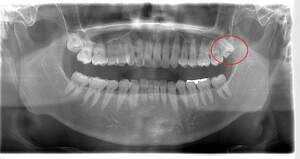

左下の歯茎が腫れている親知らずの症例

- 抜歯前写真(レントゲン、CT等)

左下の親知らず周囲歯肉が腫れていました。

また、手前の歯との間で虫歯もできていました。

3分割して抜歯しました。